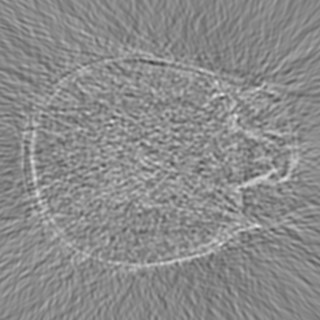

Cone-beam CT (CBCT) employs a flat-panel detector to achieve three-dimensional imaging with high spatial resolution. However, CBCT is susceptible to scatter during data acquisition, which introduces CT value bias and reduced tissue contrast in the reconstructed images, ultimately degrading diagnostic accuracy. To address this issue, we propose a deep learning-based scatter artifact correction method inspired by physical prior knowledge. Leveraging the fact that the observed point scatter probability density distribution exhibits rotational symmetry in the projection domain. The method uses Gaussian Radial Basis Functions (RBF) to model the point scatter function and embeds it into the Kolmogorov-Arnold Networks (KAN) layer, which provides efficient nonlinear mapping capabilities for learning high-dimensional scatter features. By incorporating the physical characteristics of the scattered photon distribution together with the complex function mapping capacity of KAN, the model improves its ability to accurately represent scatter. The effectiveness of the method is validated through both synthetic and real-scan experiments. Experimental results show that the model can effectively correct the scatter artifacts in the reconstructed images and is superior to the current methods in terms of quantitative metrics.